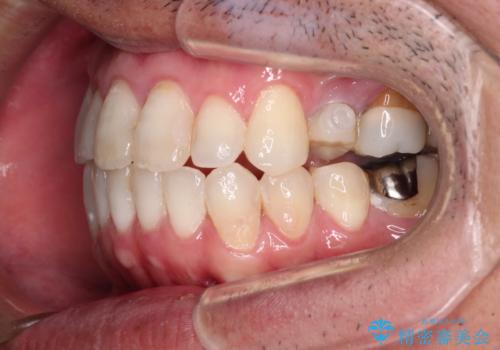

ボロボロとなっていた歯は抜歯が必要な状態でしたが、舌側転位している歯を移動させることで抜歯スペースを埋めることができるため、矯正治療により歯列を整えることとしました。

矯正治療後には抜歯が必要な歯に隣接してむし歯となっていた歯をオールセラミッククラウンにて補綴治療を行うこととしました。

矯正治療開始時に、インビザライン矯正の加速装置を購入されましたが、インビザライン自体をあまりしっかりと使用できず、4年間の治療期間となりました。